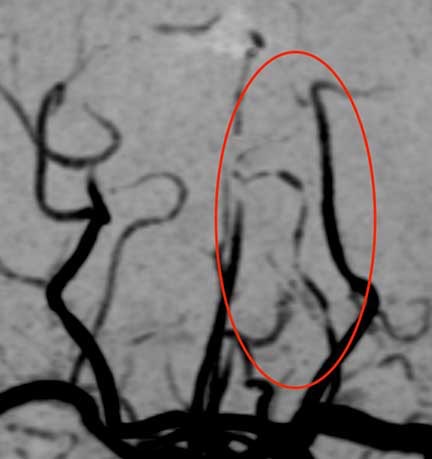

頭部MRA検査(MRIを用いた血管撮影)で脳の血管を見たところ、

後大脳動脈という後頭部から上へ行く血管が、所々で途切れたようになっています。